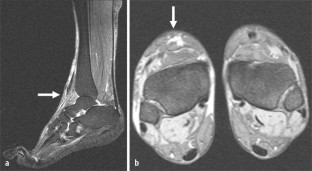

Abb. 2